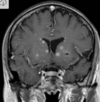

Q

A

Esclerose mesial temporal

Observe a perda de volume, que indica atrofia e causa aumento secundário do corno temporal do ventrículo lateral.

O sinal alto no hipocampo reflete a gliose.

How well did you know this?

Qual o padrão da Esclerose mesial temporal?

Atrofia hipocampal e hipersinal T2. Cerca de 10% dos casos são bilaterais (dificulta o diagnóstico). A etiologia é desconhecida, mas há uma relação entre STM e convulsões febris prolongadas no início da vida A esclerose mesial temporal pode ocorrer em associação com outras patologias, principalmente displasia cortical focal (dual pathology).